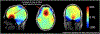

In magnetic resonance imaging (MRI), inhomogeneity in the main magnetic field used for imaging, referred to as off-resonance, can lead to image artifacts ranging from mild to severe depending on the application. Off-resonance artifacts, such as signal loss, geometric distortions, and blurring, can compromise the clinical and scientific utility of MR images. In this review, we describe sources of off-resonance in MRI, how off-resonance affects images, and strategies to prevent and correct for off-resonance. Given recent advances and the great potential of low-field and/or portable MRI, we also highlight the advantages and challenges of imaging at low field with respect to off-resonance.